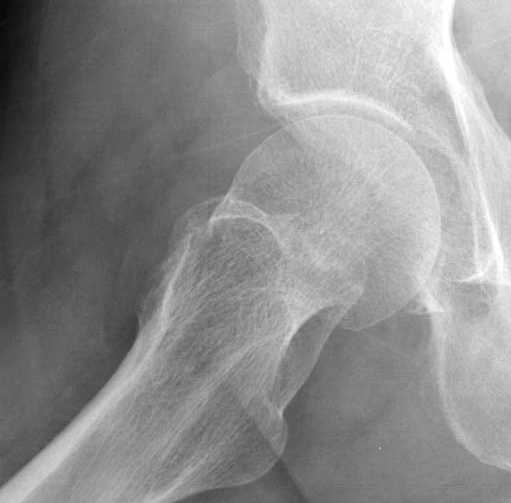

неполный перелом шейки

в течение первых 72 часов после перелома, остеосинтез тремя спонгиозными шурупами.

Почему неполный перелом? Я бы назвал его вколоченным!

Перелом конечно не вколоченный т.к. видно линию перелома и нет суперпозиции костной ткани.

Добрый день. Перелом коварный. Через время может произойти лизис в области "неполного" перелома и он превратиться в "полный" со всеми очевидными проблемами, тем более у пациента, склонного к питию. Если не разовьется делирий или после выхода из него, рекомендую внутренний остеосинтез винтами.

Профилактику дальнейшего раскола неполного перелома шейки провели тремя канюлированными шурупами.